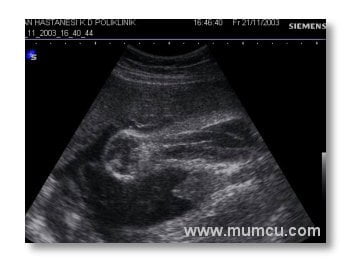

24 haftalık gebelikte kalbin 4 odacık halinde görünümü

Abdominal ultrasonografi